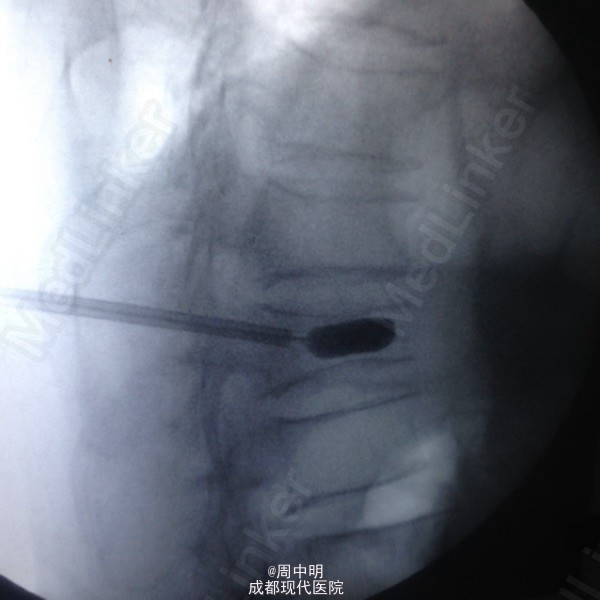

87岁,男性,T11压缩骨折

胸椎11压缩骨折